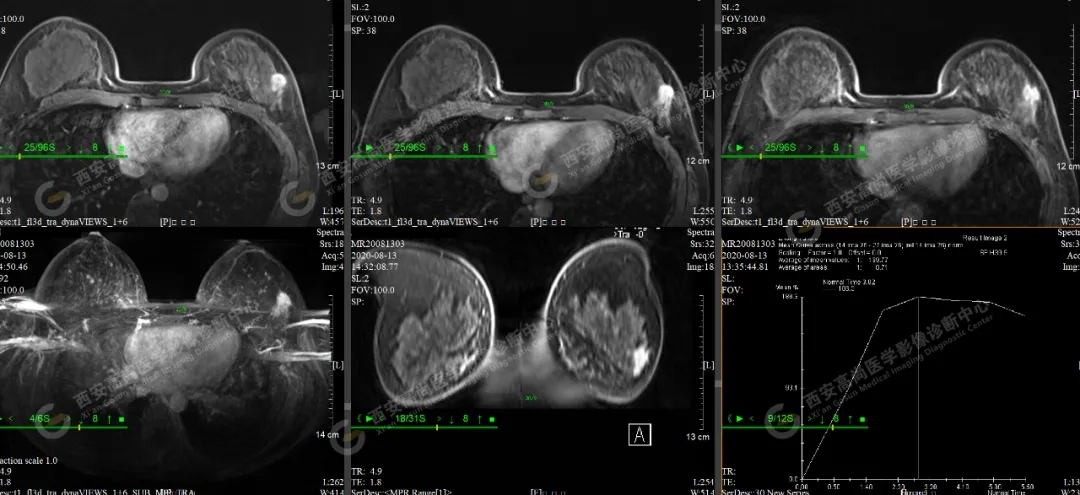

【病例二】女,46歲,左側(cè)乳腺5點(diǎn)方向乳腺Ca(BI-RADS IV-V級(jí)),左側(cè)腋窩多發(fā)腫大淋巴結(jié)轉(zhuǎn)移。